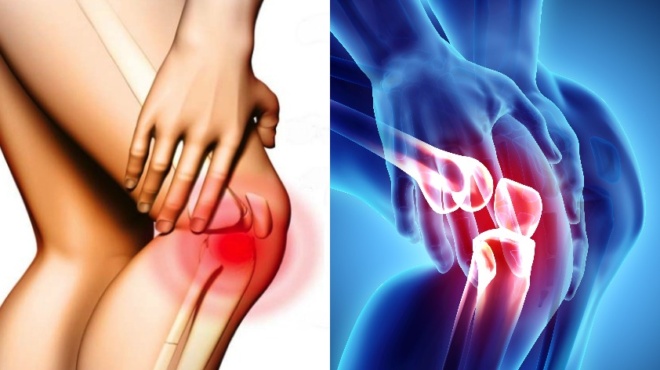

Συμβουλές υγείας: Επώδυνες καταστάσεις, που σχετίζονται με τη φλεγμονή

– Οστεοαρθρίτιδα

Απλά συμπτώματα

– Ερυθρότητα

– Διογκωμένες αρθρώσεις

– Πόνος αρθρώσεων

– Δυσκαμψία αρθρώσεων

– Απώλεια λειτουργικότητας στην άρθρωση